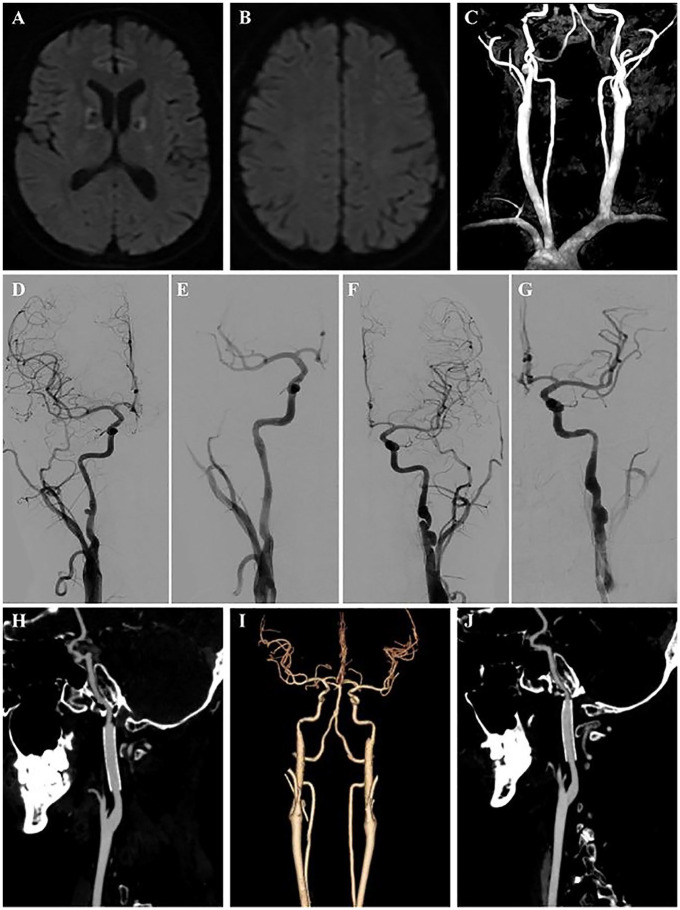

A case of spontaneous bilateral internal carotid artery dissection (ICAD) in a 36-year-old male, potentially linked to COVID-19, is reported. Initially presenting with excessive daytime sleepiness, an atypical symptom for ICAD, the patient lacked focal neurologic deficits. Diagnostic evaluation revealed severe stenosis and dissecting aneurysms in both carotid arteries. Treatment included anticoagulation, corticosteroid therapy, and subsequent endovascular stent placement. This case underscores the importance of considering ICAD as a potential complication of COVID-19, especially in patients with atypical symptoms. Further research is needed to understand the underlying mechanisms and optimize treatment strategies.

Abstract Image